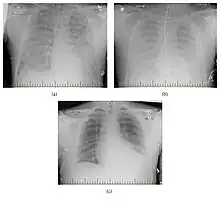

Radiographic progression of hantavirus pulmonary syndrome from presentation, being placed on ECMO two days later, to improvement after 10 days